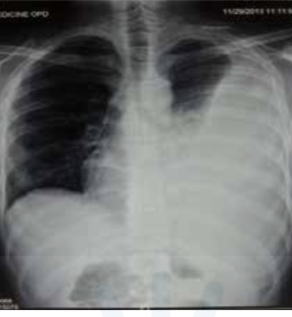

Radiological diagnosis of pleural effusion

Meniscus sign / Ellis S curve